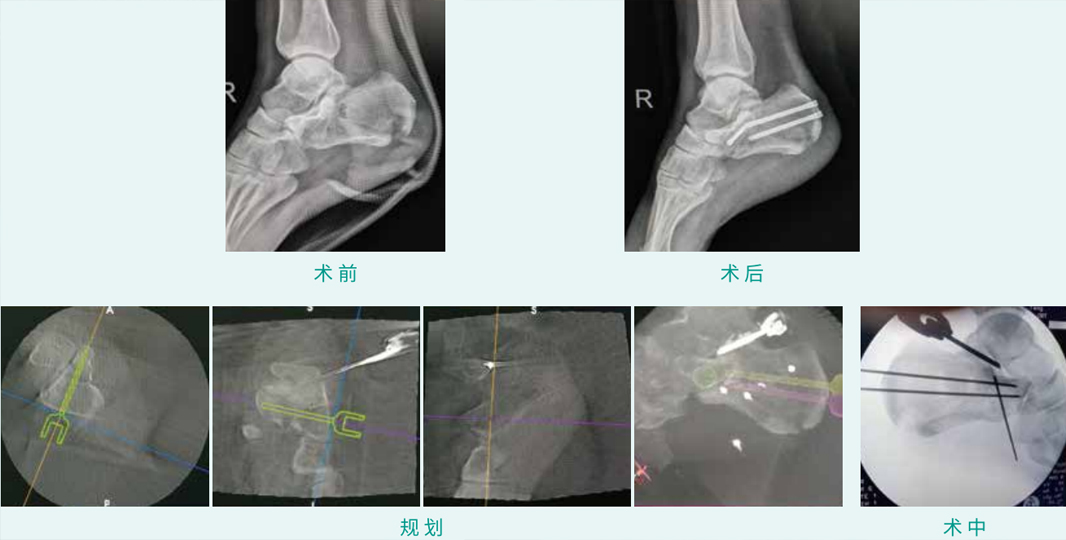

TiRobot ? Calcaneus Fracture Percutaneous Screw Fixation

天玑? 辅助跟骨骨折经皮空心螺钉内牢靠术

基本情形:患者男,27岁,跟骨骨折

机械人累积用时:30分钟

植入物:3枚空心螺钉

病例泉源:四川省人民医院 张斌 唐智